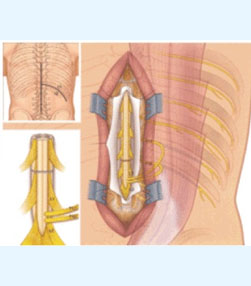

- Spine surgery - More than 3000 spinal surgeries including 40 spinal tumors microdiscectomy, MIS TLIF, artificial disc replacements, multilevel corpectomy, CV junction stabilization.

- Endoscopic brain surgeries - More than 300 endoscopic third ventriculostomies, 30 ventricular tumors.